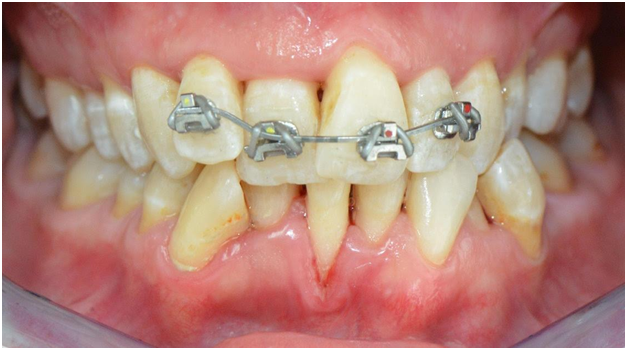

The patient received scaling and root planing followed by the application of brackets on the four maxillary anterior teeth for patient comfort (Figures 4). A subsequent appointment specifically addresses the application of brackets on the lingually inclined teeth while avoiding bracket application on labially inclined teeth (Figure 5). As the roots of previously lingually inclined teeth upright, brackets are placed on all teeth at a subsequent appointment (Figure 6). Clinical results along with photographs comparing pre and post treatment show dramatic periodontal and esthetic improvement, particularly with alveolar bone development and the reversal of recession (Figure 7). Treatment results are impressive as uprighting of the malpositioned roots creates remodeling of alveolar bone to accommodate the boney support of the properly aligned tooth. Post-treatment results also show a stable occlusion with proper overjet and overbite relations.

Figure 4 After scaling of teeth and application of four brackets on the maxillary anterior teeth for patient comfort, (Courtesy of Dr. Patrick Assal, Lausanne Switzerland).

Figure 5 Brackets are placed on lingually inclined teeth to facilitate alveolar bone formation by creating healthy soft tissue and the elimination of cleft formation previously associated with Orthodontosis™. Note that brackets are not placed on labially positioned teeth, (Courtesy of Dr. Patrick Assal, Lausanne Switzerland).